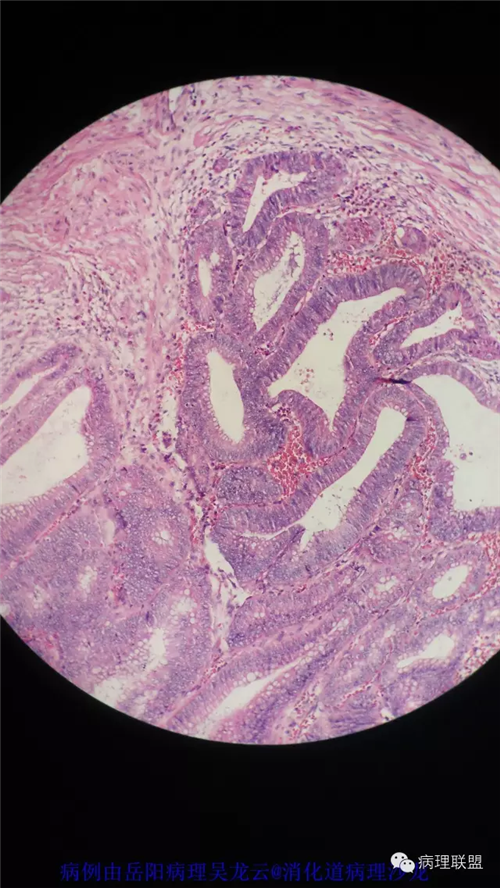

病例2

病史

女性,60岁,结肠腺瘤活检。有一灶腺体突破粘膜肌,腺体无明显异形。

(注:病例由岳阳病理吴龙云提供 致谢!)